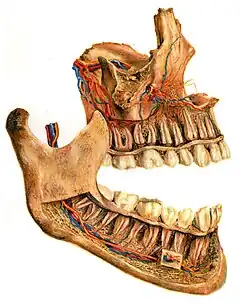

Human jaws with anterior (frontal) portion of alveolar processes cut away towards right

German illustration (c.1910) depicting interior of jawbones, with nerves, veins, and arteries leading to teeth—and thus the alveolar area

On the maxilla, the alveolar process is a ridge on the inferior surface, making up the thickest part of the bone. On the mandible it is a ridge on the superior surface. The structures hold the teeth and are encased by gums as part of the oral cavity.[11] Congruent with much of the mandibular canal, the alveolar process comprises cells, nerves, blood vessels, lymphatic vessels, and periosteum.[8] The alveolar crest terminates uniformly at about the neck of the teeth (within about 1 to 2 mm in a healthy specimen).[12][13]

The alveolar process proper encases the tooth sockets, and contains a lining of compact bone around the roots of the teeth, called the lamina dura.[8] This is attached by the periodontal ligament (PDL) to the root cementum.[8] Although the alveolar process is composed of compact bone, it may be called the cribriform plate because it contains numerous holes where Volkmann's canals pass from the alveolar bone into the PDL. The alveolar bone proper is also called bundle bone because Sharpey's fibres, part of the PDL, are inserted there. Sharpey's fibres in alveolar bone proper are inserted at a right angle (just as with the cemental surface); they are fewer in number, but thicker in diameter than those found in cementum.[8]

The supporting alveolar bone consists of both cortical (compact) bone and trabecular bone. The cortical bone consists of plates on the facial and lingual surfaces of the alveolar bone. These cortical plates are usually about 1.5 to 3 mm thick over posterior teeth, but the thickness is highly variable around anterior teeth.[13] The trabecular bone consists of cancellous bone that is located between the alveolar bone proper and the cortical plates.[14]